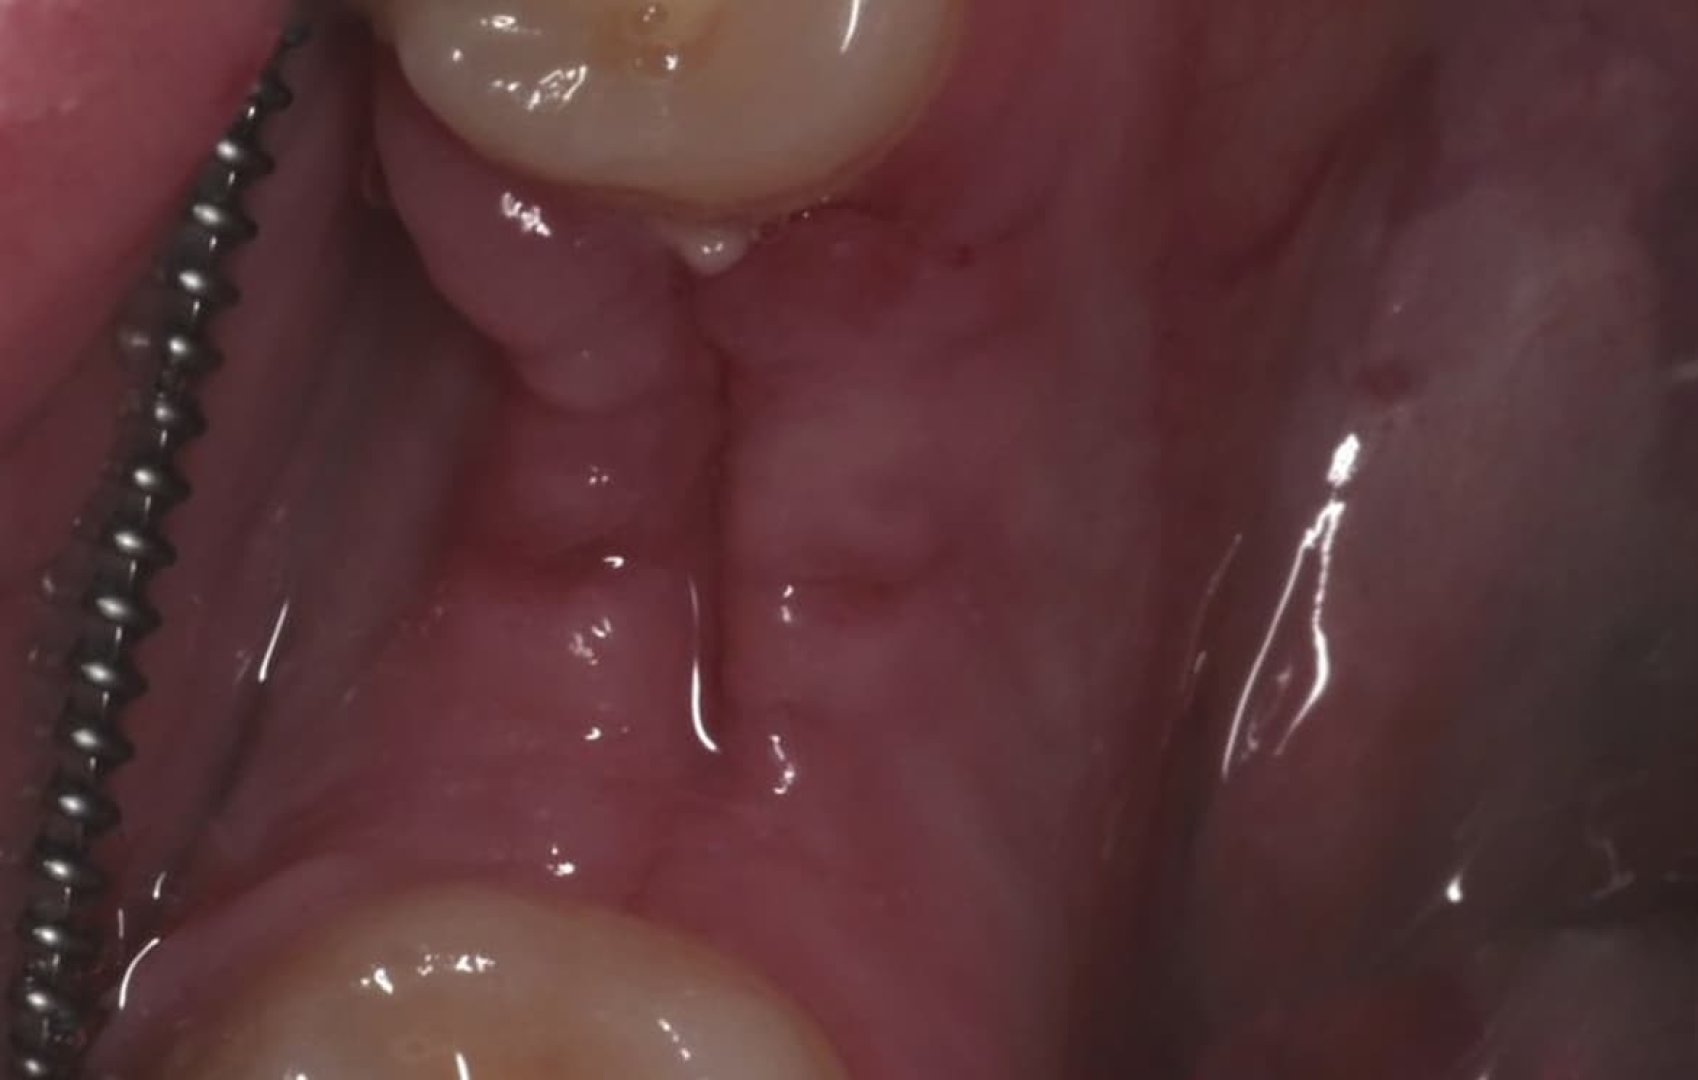

Установка имплантата с пластикой десны

Установка имплантата с пластикой десны в один этап. Фиксация коронки на имплантат через 3 месяца.